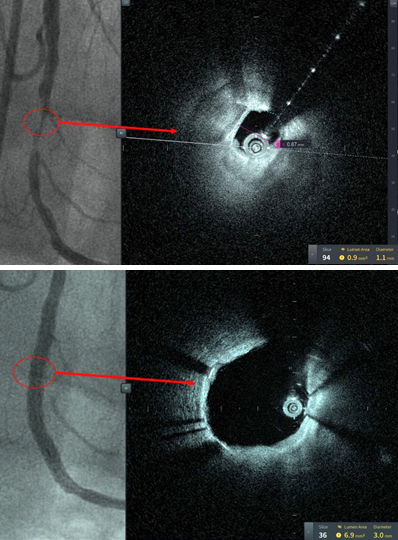

The image resolution of the Gentuity HF-OCT system provides the operator with a microscopic level of detail showing the vessel from the inside (see Figures, right). In this case, the catheter is 60% smaller than the current generation of intravascular imaging devices, which enables imaging of very narrowed blood vessels that were not previously possible.

“The case was performed on a patient with critical coronary artery disease who received three stents and the HF-OCT helped guided stent selection and optimization with excellent results. This breakthrough technology consists of a next generation high-speed laser technology that allows image acquisition of the entire vessel in one second. I am so proud of our team.”